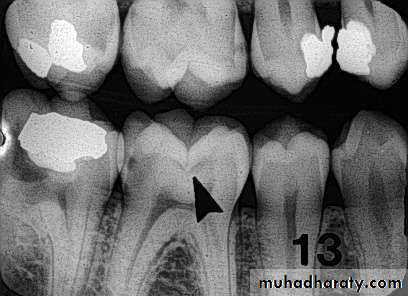

Carious lesions are detectable radio graphically when there has been enough demineralization to allow it to be differentiate from normal.They are valuable in detecting proximal caries which may go undetected during clinical examination.

On average they have around 50% to 70% sensitivity in detecting carious lesions.

40% demineralization is required for definitive decision on caries

PIT & FISSURE CARIES

Incipient occlusal lesions:Not very effective.

Caries starts on the walls

of the pits & fissures and

tends to spread

perpendicular to the DEJ

Only detectable change is

a fine gray shadow at the

DEJ.

Moderate occlusal lesions:

Moderate occlusal lesions: First to induce specific changes

helping in a definitive diagnosis

Broad based, thin radiolucent

zone in dentin with minimal or

no changes in enamel

Presence of a band of increased

opacity between the lesion and

the pulp chamber due to

calcification within primary

dentin

This feature is not seen in

buccal caries

Severe occlusal lesions:

Readily observed bothclinically and

radiographically

Appear as large cavities in

the crowns of the teeth

However pulp exposure

cannot be determined

Incipient occlusal lesions

Moderate occlusal lesionsSevere occlusal lesions

Advanced proximal lesions

Incipient proximal lesionsModerate proximal lesions